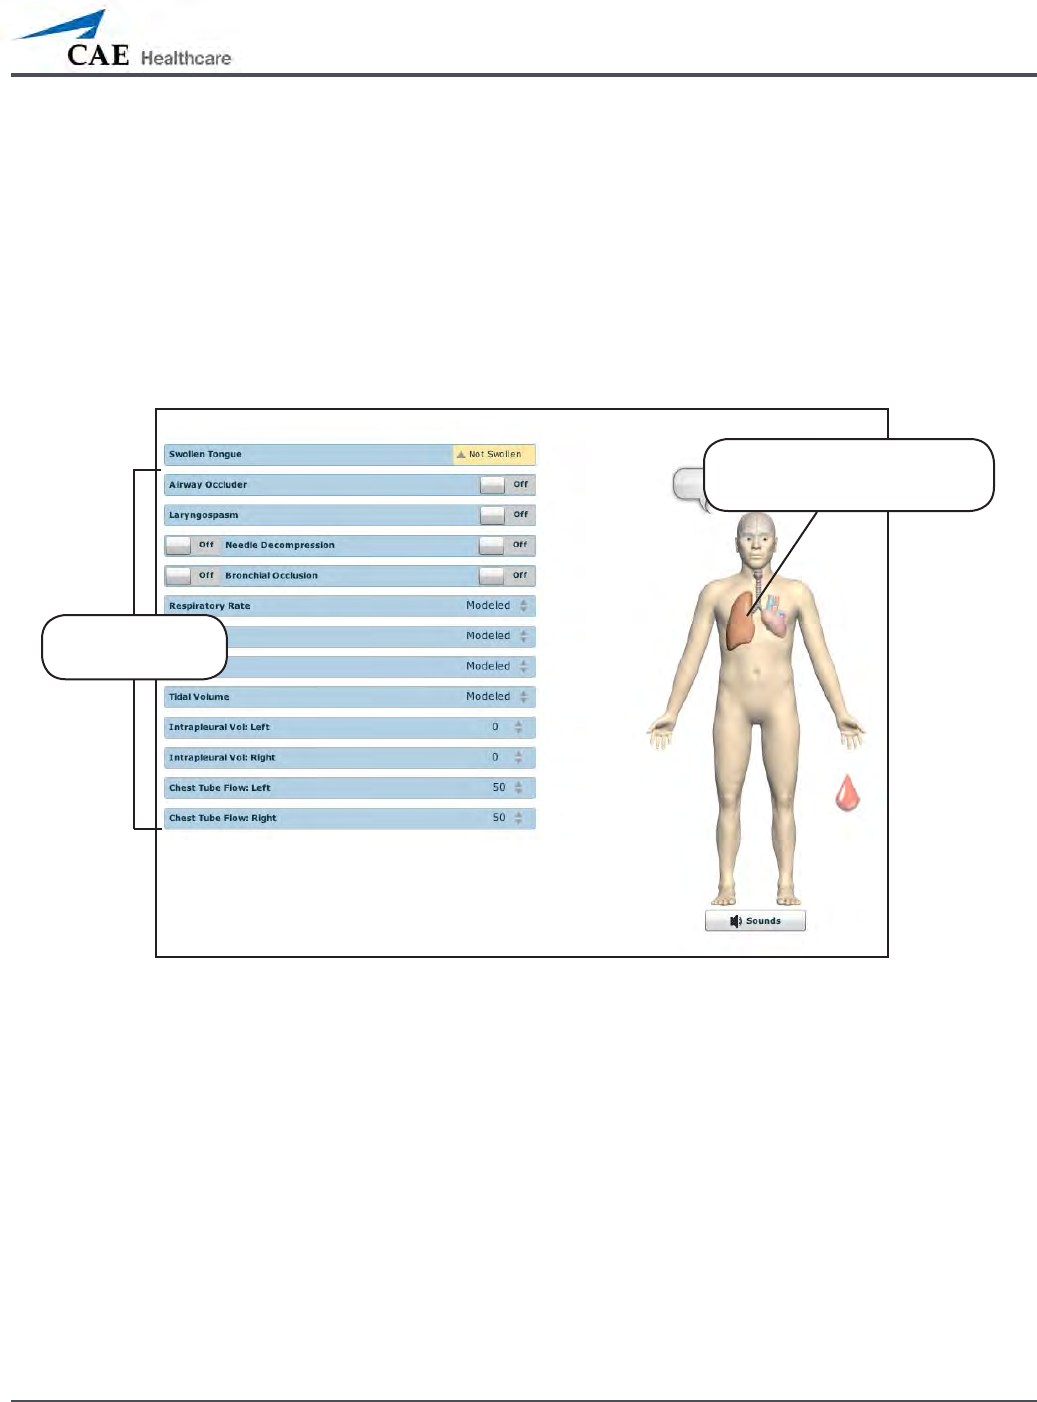

Respiratory

METIman Prehospital’s Respiratory system is comprised of the airway management,

spontaneous breathing and ventilation features. On METIman Nursing, various clinical signs

such as breath sounds, chest excursion and airway patency can be physically demonstrated.

A series of speakers inside each simulator can generate a range of breath and throat sounds

used in diagnosing conditions. To access the Respiratory parameters of METIman, on the

Run screen, click the lung on the human form. The respiratory parameters appear on the Run

screen.

The Respiratory View

Click the lung to access

the Respiratory view

Respiratory

parameters